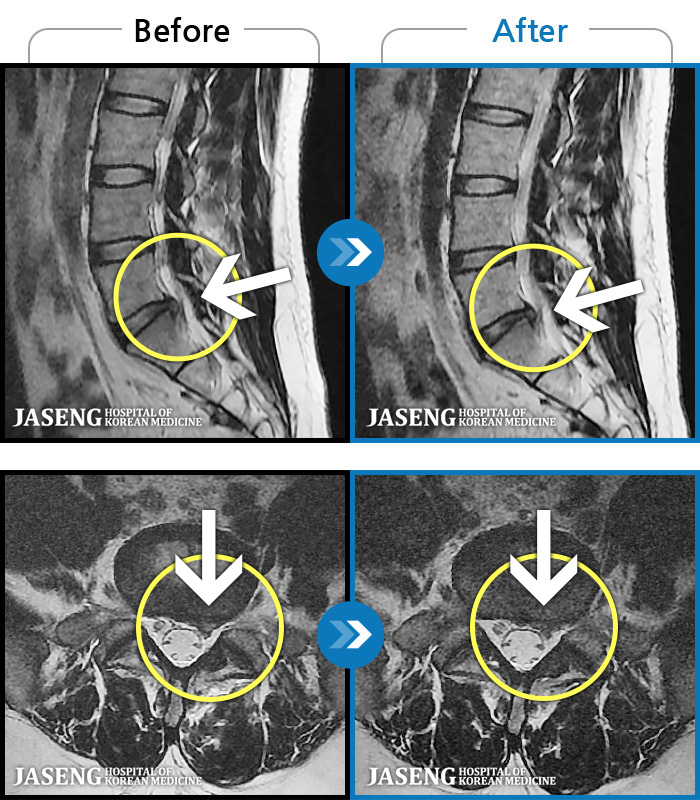

MRI ġ

1,299 MRI ũ ʸ Ȯϼ.